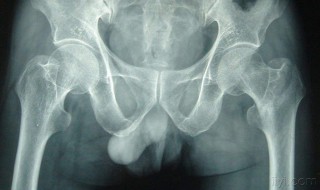

1、腰椎骨折,如果压缩不明显,可以保守治疗的,如果压缩明显,椎管有占位,那么就行手术治疗。保守治疗注意卧床休息,经常翻身,防治压疮等并发症。愈合一般要2到3个月。